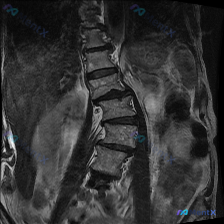

整理到一份影像资料,主诉考虑「脊柱侧弯」,但只放了一张矢状位腰椎MRI T1加权图像。 图像本身的客观表现大概是: - L1-L5椎体及骶骨轮廓清,高度大致正常,未见明显压缩骨折或滑脱 - 椎体骨髓信号中高,符合脂肪沉积,未见明确骨质破坏 - 椎间盘信号中等,椎间隙未见明显狭窄,硬膜囊前缘较完整 -...

整理了一份腰椎影像资料,用户一开始问的是“这张图能看到脊柱侧弯吗?”。先说明一下,只有这份腰椎MRI T2加权矢状位序列。 先说说图里明确能看到的: 1. 多个腰椎椎间盘信号普遍减低,考虑广泛脱水退变; 2. L4/L5、L5/S1这些下腰段椎间盘后缘向椎管内突; 3. L3/L4、L4/L5、L5...